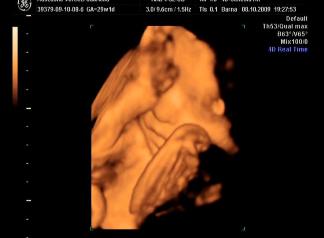

Briell! Nagyon szepek a kepek, a szemtakarosak mindig nagyon cukik, de a labikos sem semmi